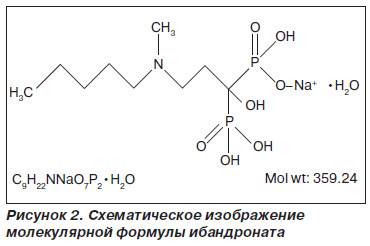

Антирезорбтивный эффект ибандроната как представителя бисфосфонатов имеет сходный механизм действия с другими азотсодержащими бисфосфонатами и направлен на снижение костного ремоделирования путем угнетения резорбции кости [8]. Структурная формула ибандроната представлена на рис. 2.